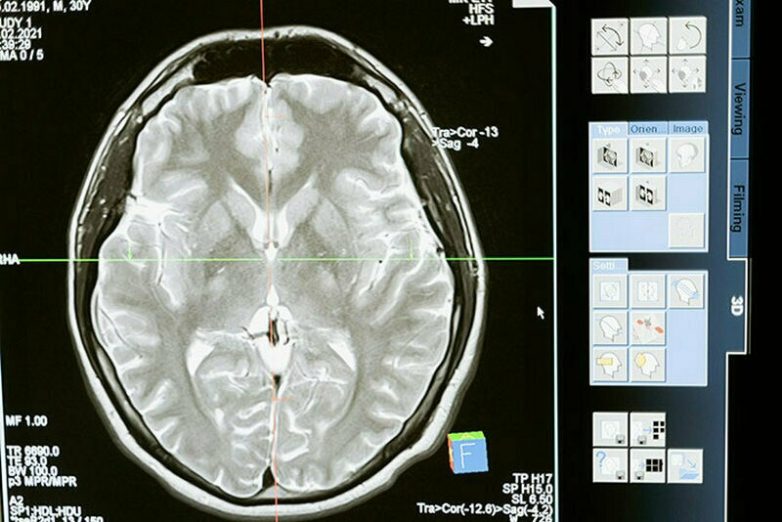

Разрыв аневризмы головного мозга может быть у каждого, даже у очень здорового человека

В 50 % случаев смерть будет мгновенной.